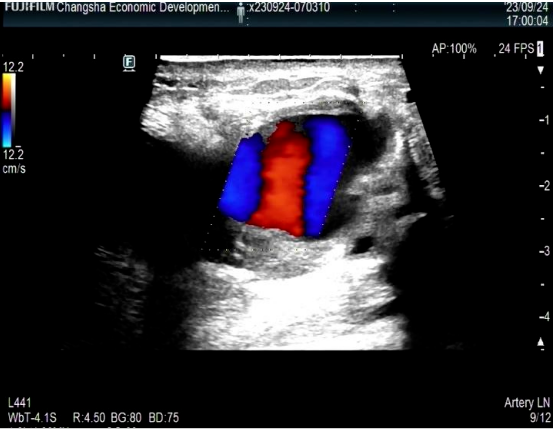

我院接诊后,医生仔细查看了以前的检查资料与病历,明白一家人的心愿是为袁女士减轻痛苦与延长生命周期。于是,特意为袁女士安排了单间,且由普外科主任胡国潢教授、肿瘤科易平勇教授等专家组成MDT多学科诊疗团队等为袁女士治疗。经过医护团队们精心的治疗、无微不至的照顾,轻声细语的排扰,从方方面面为袁女士做好专业且暖心的医疗服务。环境的舒服、医护的贴心、专业而精心的治疗为袁女士争取了多一些的时间。最终的结果谁都无法改变,但家人和医护们尽心尽力的关心与照顾,让袁女士感受了无尽的温暖与爱,减少了很多痛苦,内心变得平静和从容。